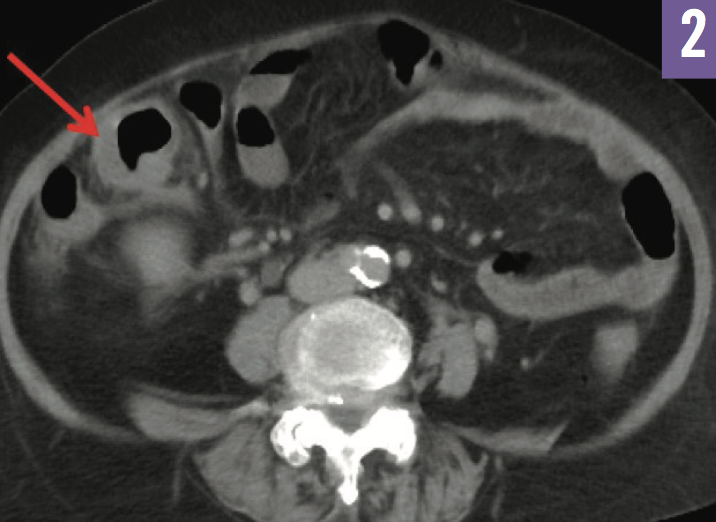

Diagnostic tests. Chest radiograph findings (Figure 1) and results of workups for infectious and hematologic etiologies were unremarkable. Serologic test results were positive for the presence of anti-Saccharomyces cerevisiae antibodies (ASCA), consistent with Crohn disease (CD). Repeat abdominal and pelvic CT scans confirmed the findings of wall thickening and edema of the distal ileum noted on the previous studies (Figure 2), but with a new finding of bilateral ovarian cystic and solid masses concerning for malignancy. Subsequent CT scans of the chest showed disseminated peripheral ground-glass nodules and an indeterminate lung nodule (Figure 3).

Figure 2: CT of the abdomen and pelvis showed wall thickening and edema of the distal ileum.